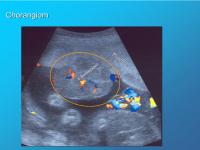

Chorangiom

Abbildung 13

Keywords: ChorangiomFarbdopplerPlazenta-Tumor